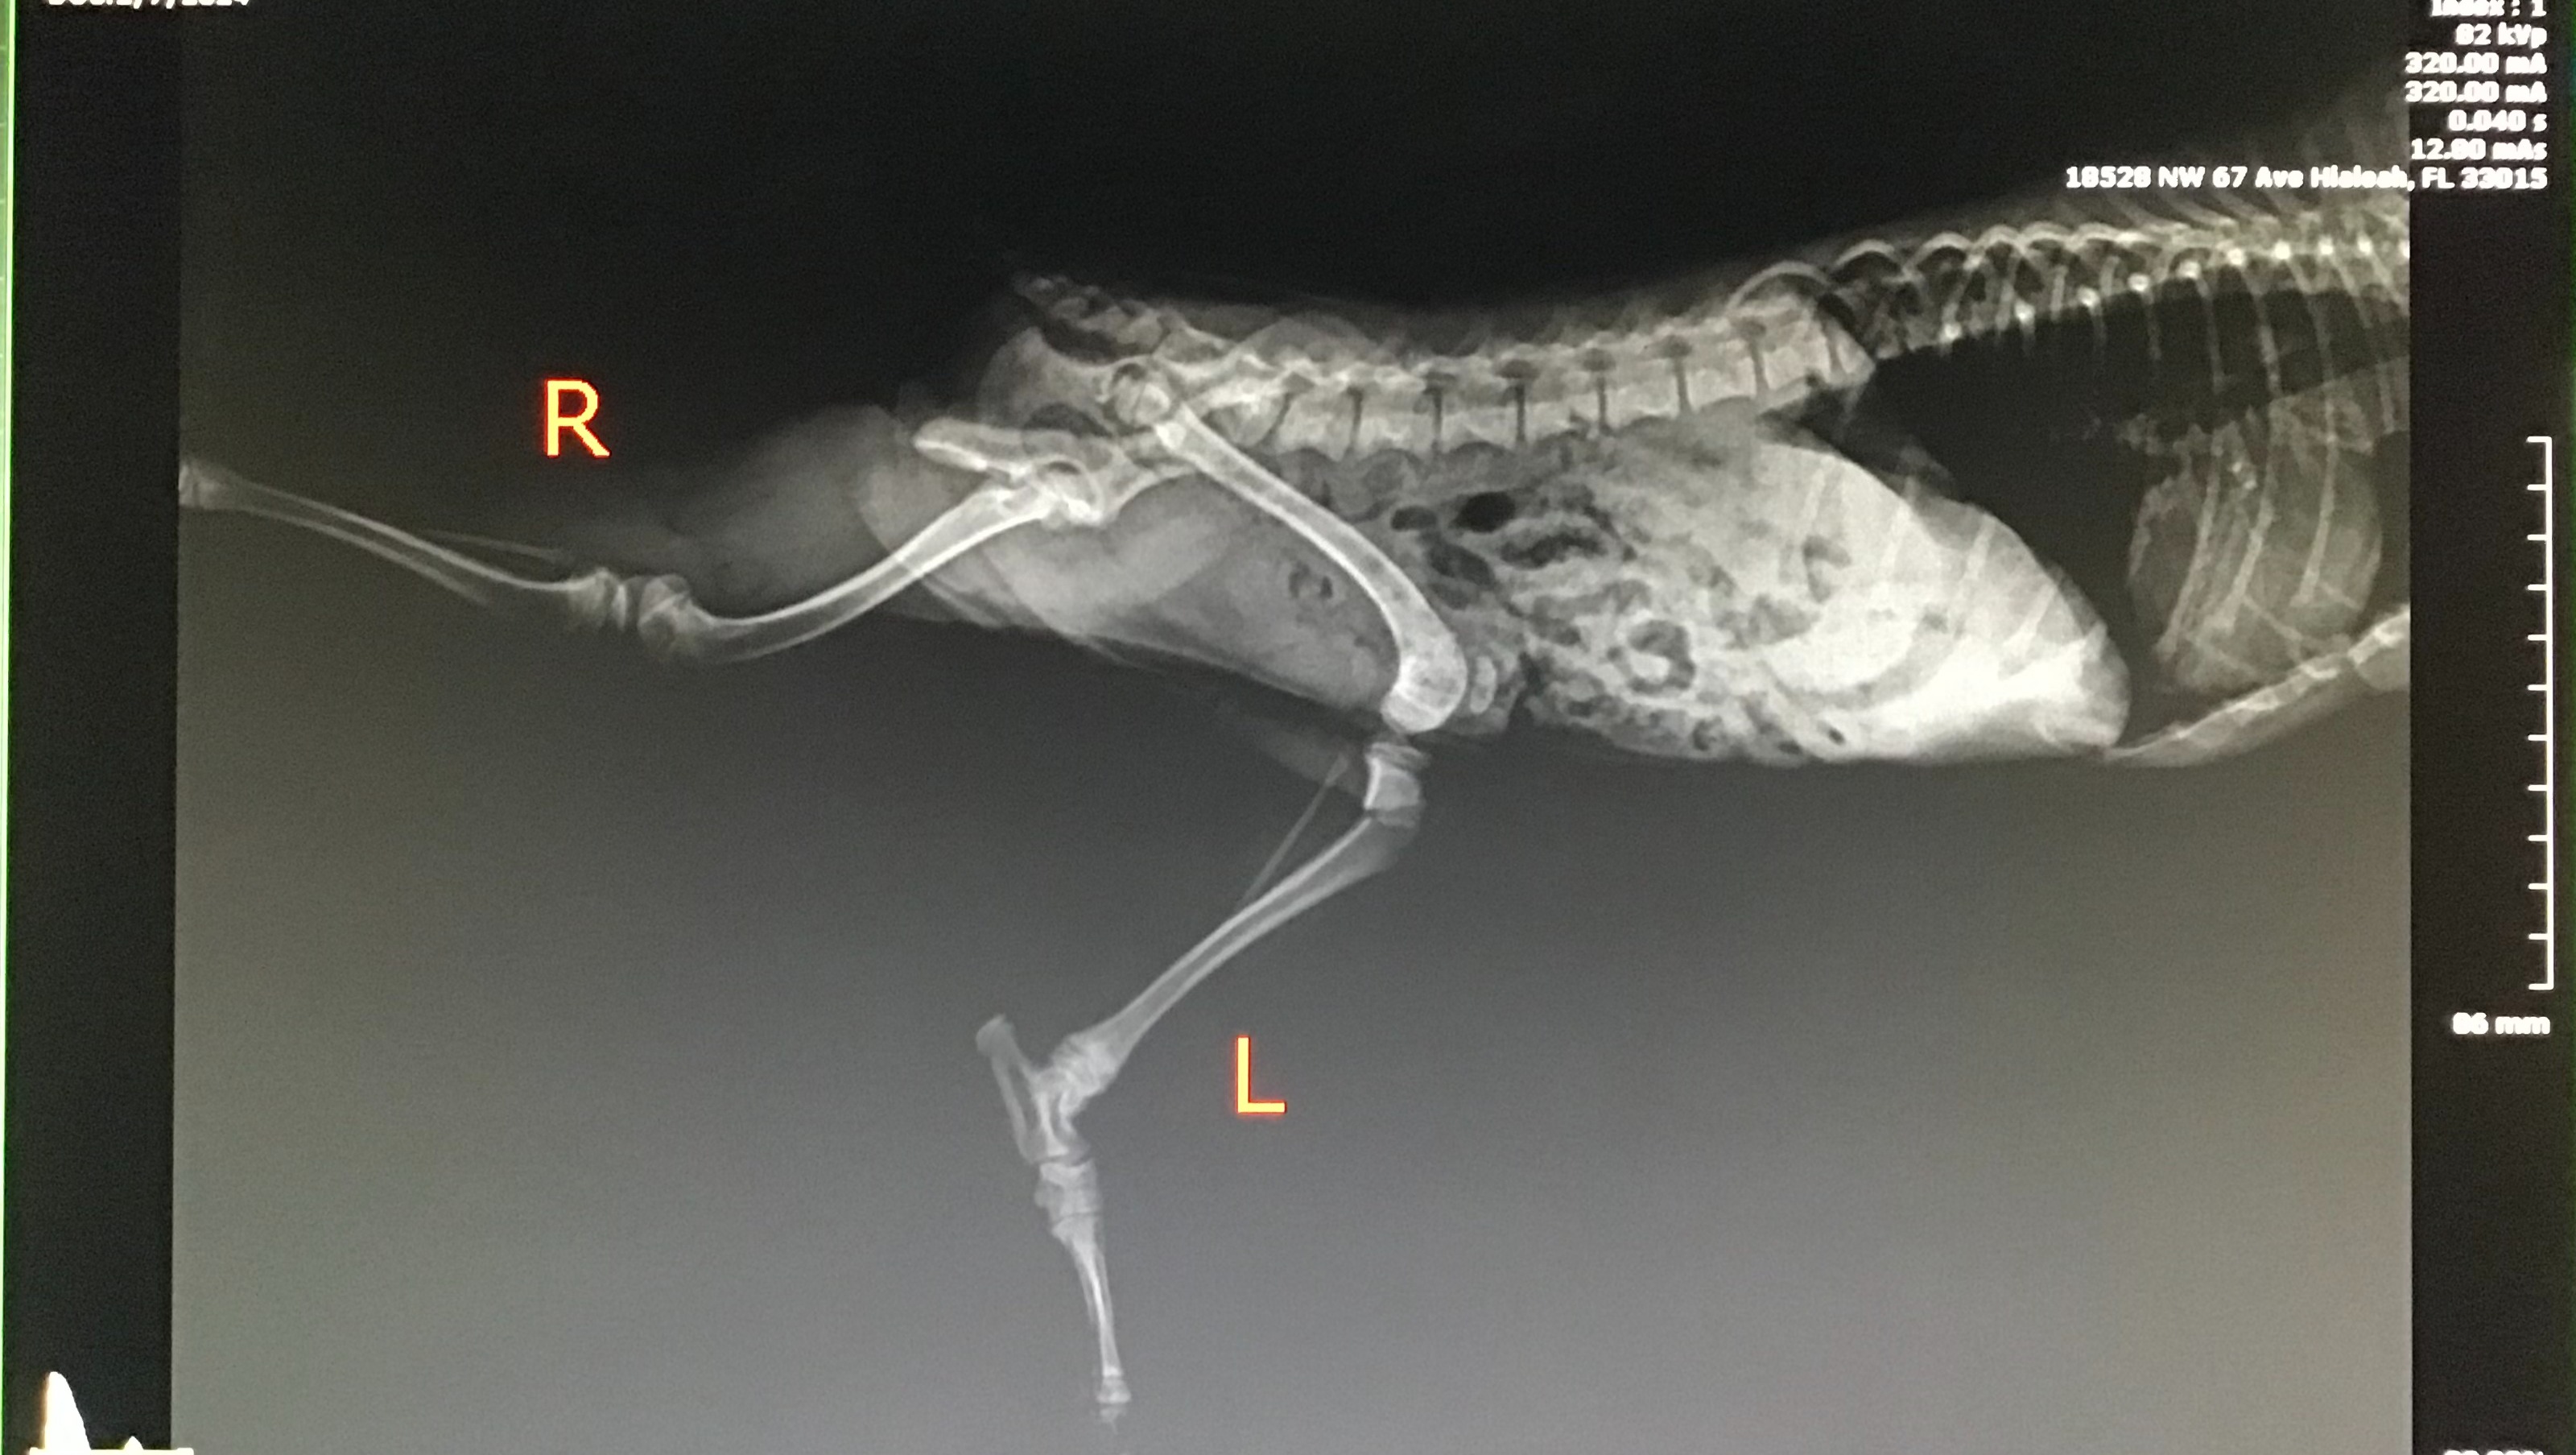

On February 07, 2024 I called to check on Tiny Tim in the morning and everything was fine I was told. I was feeling better than usual days from my traumatic brain injury symptoms and I decided to drive up to try and clean the kitchen cabinets at my new residence and pick up Tiny Tim. Well when I get there I notice he was out and about, he was so happy wagging his little tail and I proceeded to walk a bit further in and I come to realize his back left leg is completely up and he isn't moving it. I touch it and though he didn't cry he seemed like he had discomfort yet showing resilience.

I called my best friend to ask why was Tiny Tim out and he just didn't have any answer and he said he was fine. Without thinking or any hesitation I pick up Tiny Tim and take him to a Veterinarians office I had spotted when

scouting the area three minutes away. Once there they immobilized his leg to avoid further damage and as you can see he has a big fracture and the only explanation might be that he fell from the stairs because he was left out. I am angry, frustrated, in disbelief because I trusted and I shouldn't. I feel like a failed in protecting my furbaby.